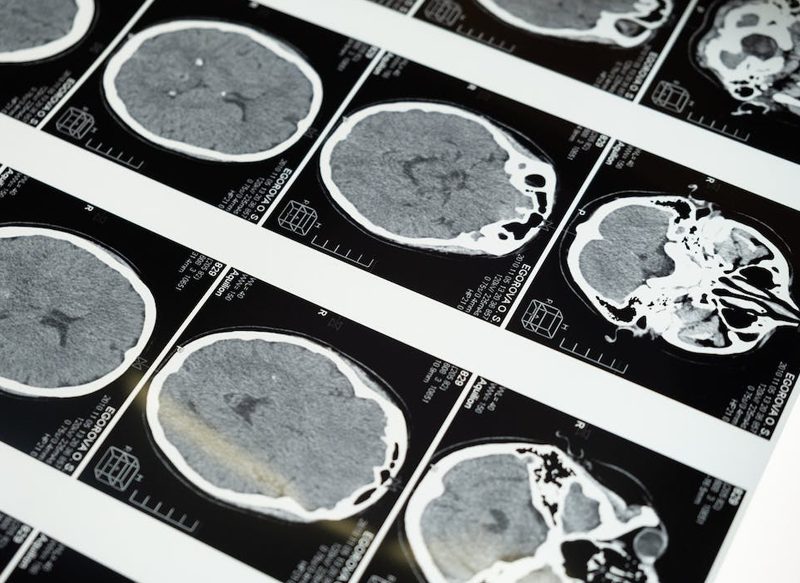

La enfermedad del Alzheimer es un trastorno cerebral que se ha situado como la causa más frecuente de demencia, que consiste en una destrucción paulatina de la memoria y la capacidad de pensar, además de realizar tareas más sencillas a medida que pasa el tiempo. Ahora el Eisai y Biogen han creado un fármaco que causa un increíble efecto en el cerebro.